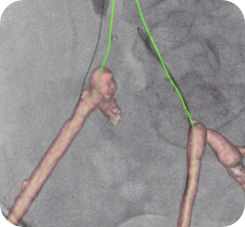

Bei peripheren, chronischen Komplettverschlüssen (CTO) bietet die Vessel ASSIST-Lösung eine intuitive und genaue Lösung, die Sie bei der Planung und Führung komplexer endovaskulärer CTO-Eingriffe unterstützt. 1

Die automatische Segmentierung von Knochen und Gefäßen und die Mittellinienverfolgung durch den Gefäßverschluss ermöglichen eine schnelle Planung anhand von präoperativen CT- oder MR-Bildern. Durch diese Kombination präoperativer CT- oder MR-Bilder mit Mittellinienverfolgung und Durchleuchtung in Echtzeit können Spezialisten außerordentlich gut sehen, wo die Rekanalisation vorgenommen werden muss und wo sich die Einstichstelle befindet, ohne die Kontrastmittelmenge erhöhen zu müssen.